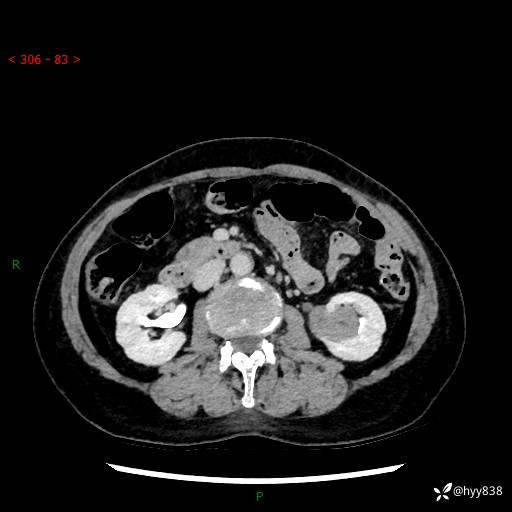

72岁/女,检查发现左肾占位1天。为了满足诊断,常规四期后,又加了延迟期-结果公布~

【患者信息】:72岁/女

【主诉】:检查发现左肾占位1天

【现病史及既往史】:患者于1天前检查发现左肾占位,无畏寒发热,无咳嗽咳痰,无腰腹部疼痛不适,无肉眼血尿、无尿频尿急症状,起病来,患者未行特殊治疗,为求进一步诊治,门诊以"左肾占位"收治入院。 发病来患者精神、饮食、睡眠良好,小便如上,大便正常,体重无明显变化。

【检查】:肾脏CT平扫+增强